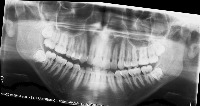

downloadClasses (32)

tooth_11

tooth_12

tooth_13

tooth_14

tooth_15

tooth_16

tooth_17

tooth_18

tooth_21

tooth_22

tooth_23

tooth_24

tooth_25

tooth_26

tooth_27

tooth_28

tooth_31

tooth_32

tooth_33

tooth_34

tooth_35

tooth_36

tooth_37

tooth_38

tooth_41

tooth_42

tooth_43

tooth_44

tooth_45

tooth_46

tooth_47

tooth_48